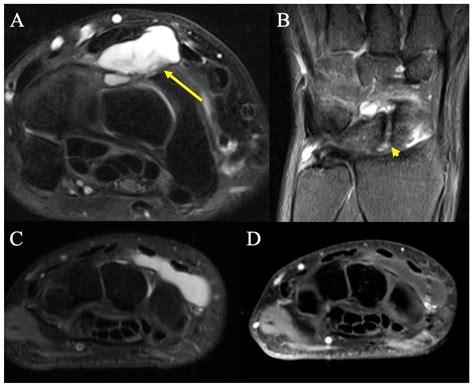

An MRI of hand can reveal a variety of conditions and injuries. Some of the most common findings include:

• Fractures: Detailed images of bone fractures, including hairline fractures that may not be visible on X-rays.

• Tendon Injuries: Tears or inflammation in the tendons, which can cause pain and limited mobility.

• Ligament Injuries: Tears or sprains in the ligaments, which can affect joint stability.

• Arthritis: Signs of joint degeneration, inflammation, and bone spurs.

• Carpal Tunnel Syndrome: Compression of the median nerve in the wrist, causing numbness and tingling in the hand.

• Tumors and Cysts: Benign or malignant growths within the hand tissues.